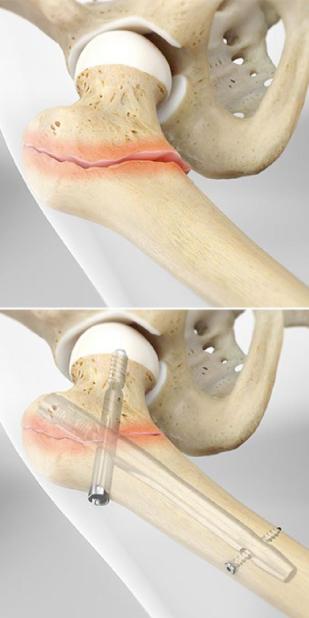

كسر عنق الفخذ أودى بالخالة فلك طريحة الفراش

كسر عنق الفخذ أودى بالخالة فلك طريحة الفراش، لا تقوى على الحركة، وتتألم بشكل مستمر، تعيش الخالة مع عائلتها في ...